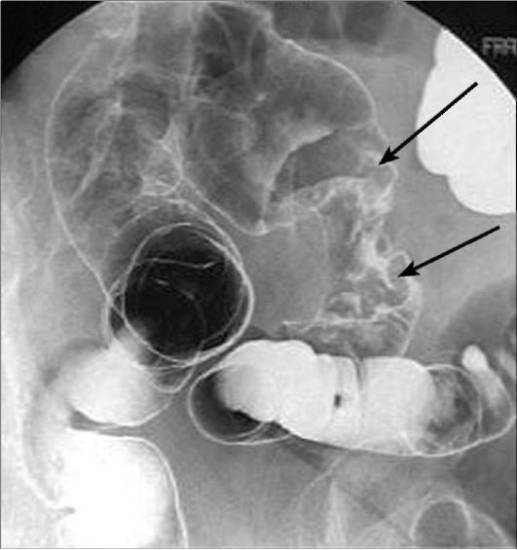

- ирригоскопия и –графия – в толстый кишечник вводят контрастное вещество, выполняют рентгенологический осмотр на экране и делают рентгенологические снимки. Полипы выявляют благодаря тому, что они выделяются на фоне контрастного вещества. Если размер полипозных выростов составляет менее 1 см, то информативность метода снижается – эту проблему решают, привлекая другие методы диагностики;